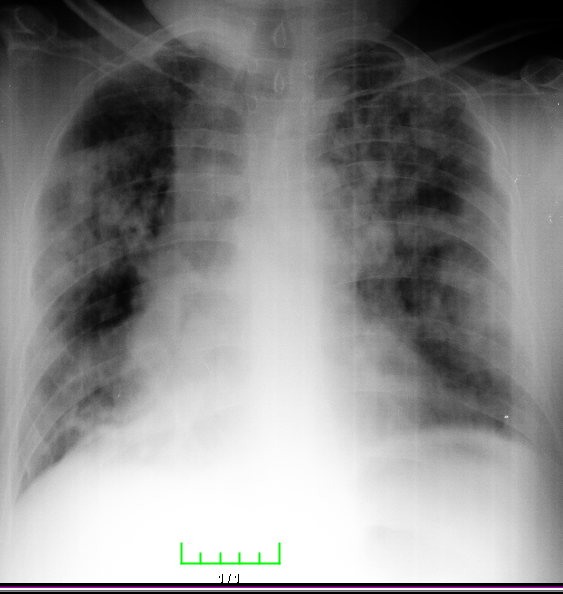

A 40-year-old male patient was admitted to our clinic with complaints of persistent cough for 10 days, phlegm, respiratory distress, fever at intervals, knee pain, and fatigue particularly increased for the past two days. During physical examination, the patient was conscious with poor orientation and cooperation, and was agitated and drowsy. His medical history was able to be obtained from his relatives due to his limited cooperation and orientation. He had a medical history of 20-packyears of smoking and brucellosis 13 years prior. He had a fever of 38.5°C, heart rate was 113 bpm, blood pressure was 100/60 mmHg, and respiration rate was 32/min. Lung auscultation showed bilateral, widespread crepitant rales in all zones of the lungs. Lung sounds were not present in the right basal lung, and dullness was detected with percussion. Cardiovascular examination findings were normal, except for tachycardia. Abdominal examination showed no signs of defense, rebound, or tenderness. Extremities were normal; however, circulatory impairment and cyanosis were present in the periphery. Laboratory test results were as follows: leukocyte 19,900/mm3, hemoglobin 13.7g/dL, hematocrit 40%, platelet count 270,000/mm3, erythrocyte sedimentation rate (ESR) 88mm/hour, and C-reactive protein (CRP) was 15.1 mg/dL. Arterial blood pressure analysis showed that pH was 7.29, PO2 was 76 mmHg, pCO2 was 22mmHg, HCO3 was 11mmol/L, and satO2:94%. Biochemical analysis of blood showed a Na level of 122mmol/L, aspartate aminotransferase (AST) level of 306 IU/mL, and alanine aminotransferase (ALT) of 143.6IU/mL. Metabolic acidosis was present in the arterial blood gas. A posteroanterior radiograph showed bilateral pneumonic infiltration and pleural effusion on the right side (Figure 1). Thoracic computed tomography (CT) showed multiple opacities and right-sided pleural effusion (Figure 2). Serum agglutination titer for Brucella was 1:320. Pleural fluid obtained on thoracentesis was consistent with exudate and hemorrhagic. Pleural fluid tested positive for Rose-Bengal test. Based on clinical and physical examination findings, the patient was diagnosed with brucellosis with lung and pleural involvement. The patient was initiated on ceftriaxone 2 g bid, doxycycline 100 mg bid, and rifampicin 600 mg once daily. His general condition improved on Day 15 of treatment and did not have fever for five days. He was discharged with the recommendation of outpatient follow-up visits. Doxycycline 100 mg bid and rifampicin 600 mg once daily treatment was scheduled to continue until two months (Figures 3 & 4).

Figure 1